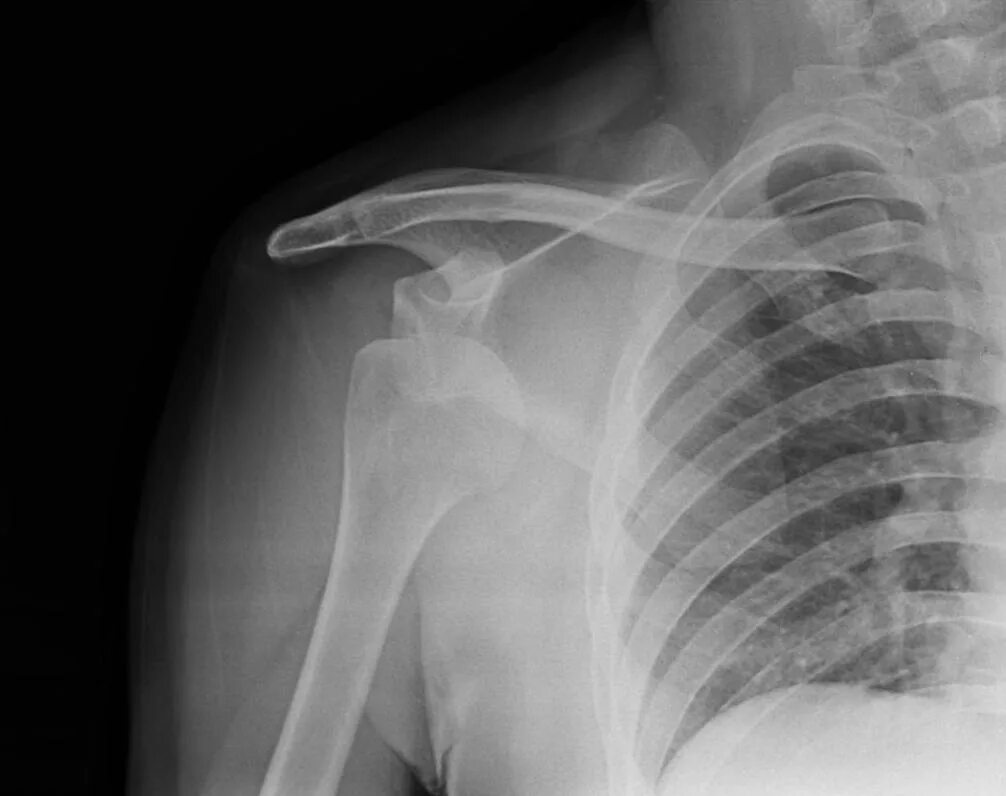

Вывих плеча вверх